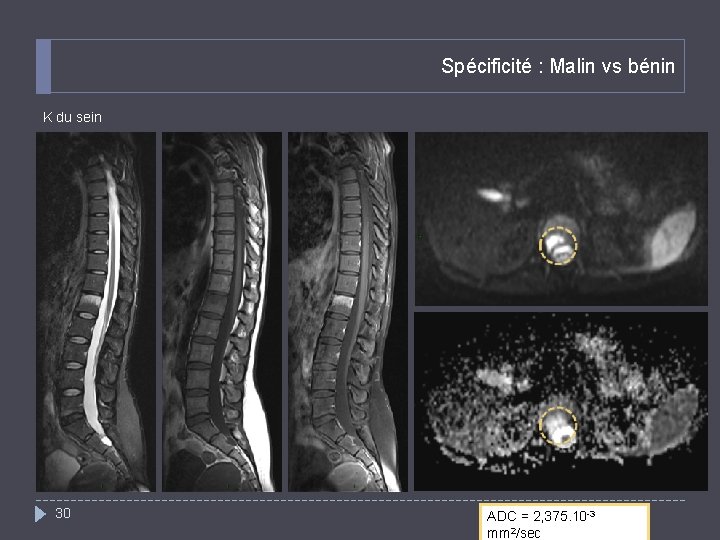

Spécificité : Malin vs bénin K du sein 30 ADC = 2, 375. 10 -3 mm 2/sec